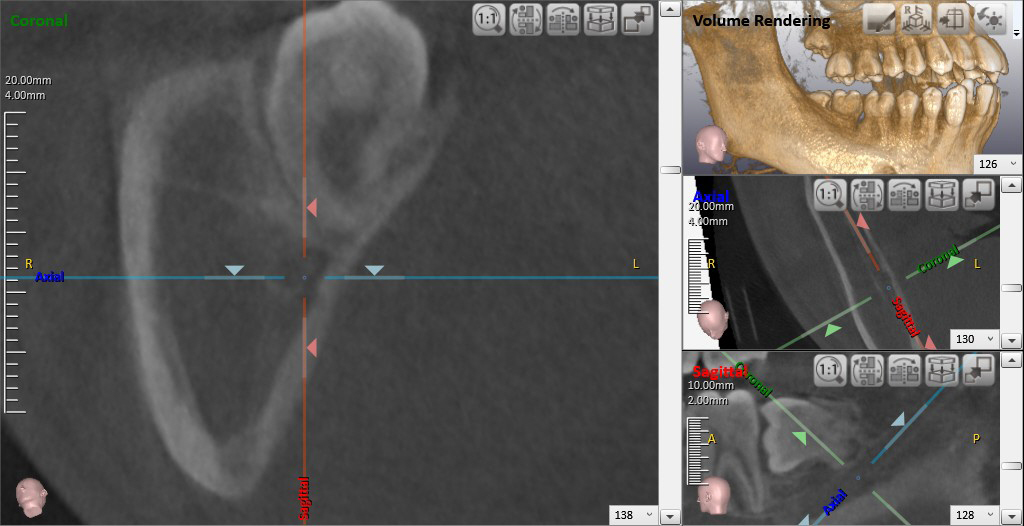

➤で囲まれた部分の顎骨内病変(鼻口蓋管嚢胞)の状態を3次元的に把握することができます。